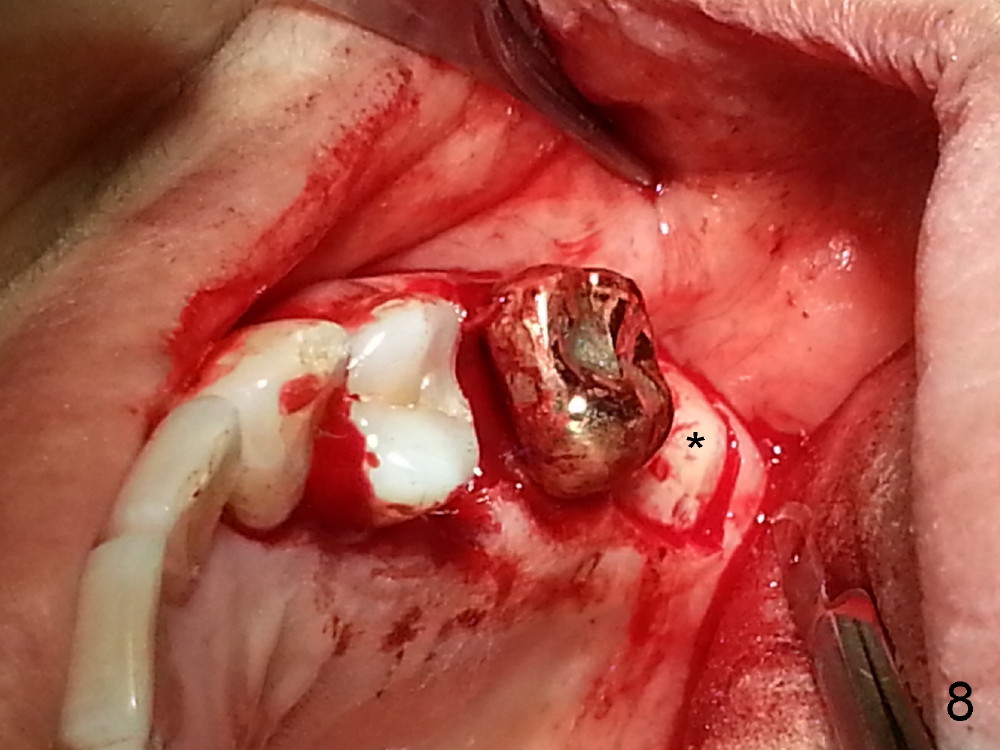

Grafting Following Immediate Implant (Photos Provided by Xue Steven, DDS)

The tooth #13 appears to be affected by periodontits and occlusal trauma (Fig.1*). After using a periotome (Fig.2), the tooth is extracted (Fig.3). The buccal flap is raised (Fig.4). Gingival graft is to be harvested from the site of #15 (Fig.5). The tissue is elevated buccally (Fig.6) and separated (Fig.7). The donor site is covered by a collagen membrane (Fig.8*). A diamond bur is used to induce bleeding from the socket (Fig.9*). Osteotomy is initiated (Fig.10) and enlarged (Fig.11,12). A tapered implant is being placed (Fig.13-15) following internal sinus lift (Fig.16,17). The implant is placed subcrestally, followed by bone graft (Fig.18), soft tissue graft (Fig.19), and suturing (Fig.20 <, Fig.21).